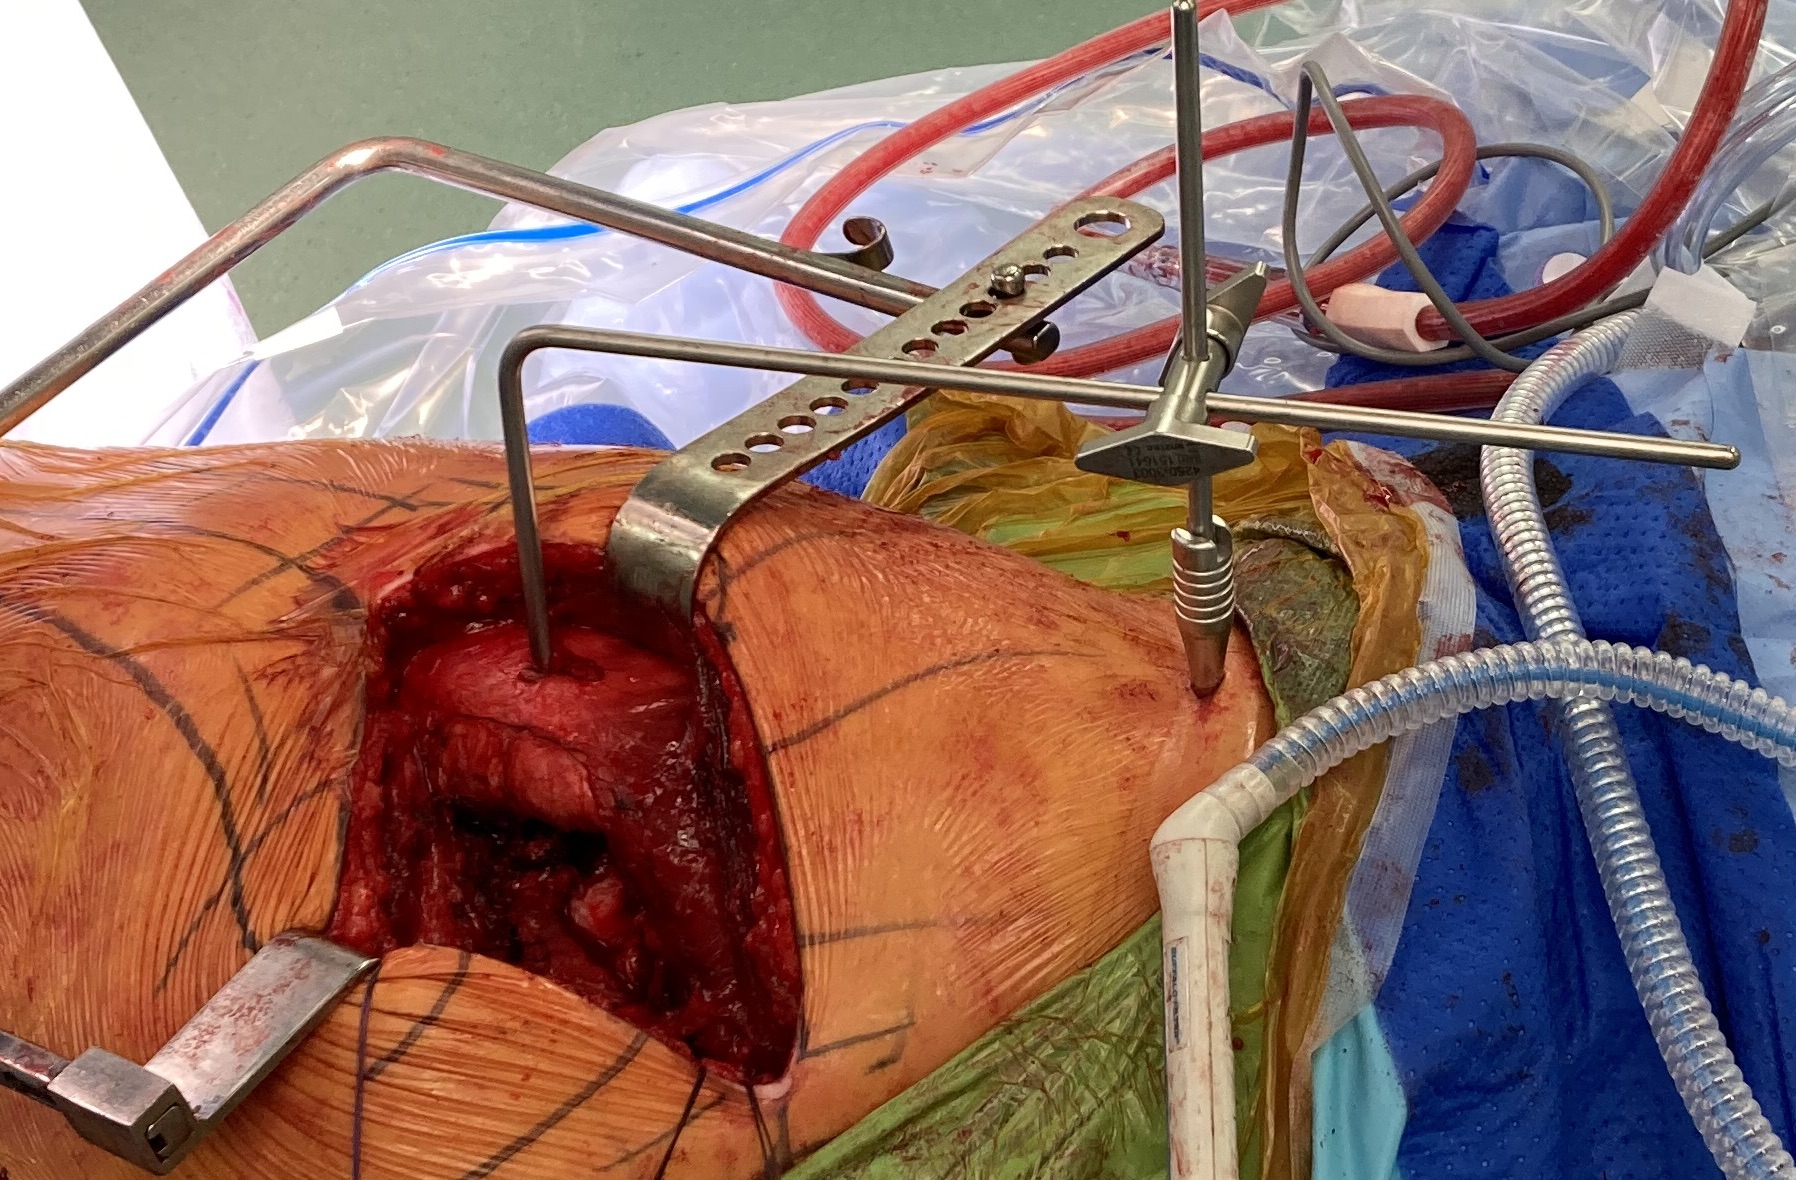

2. Intra-operative measurement

Offset jigs

Measurement jigs

- 2 fixed reference points

- pelvic landmark and femoral landmark

- limb in consistent position

- measure length and offset